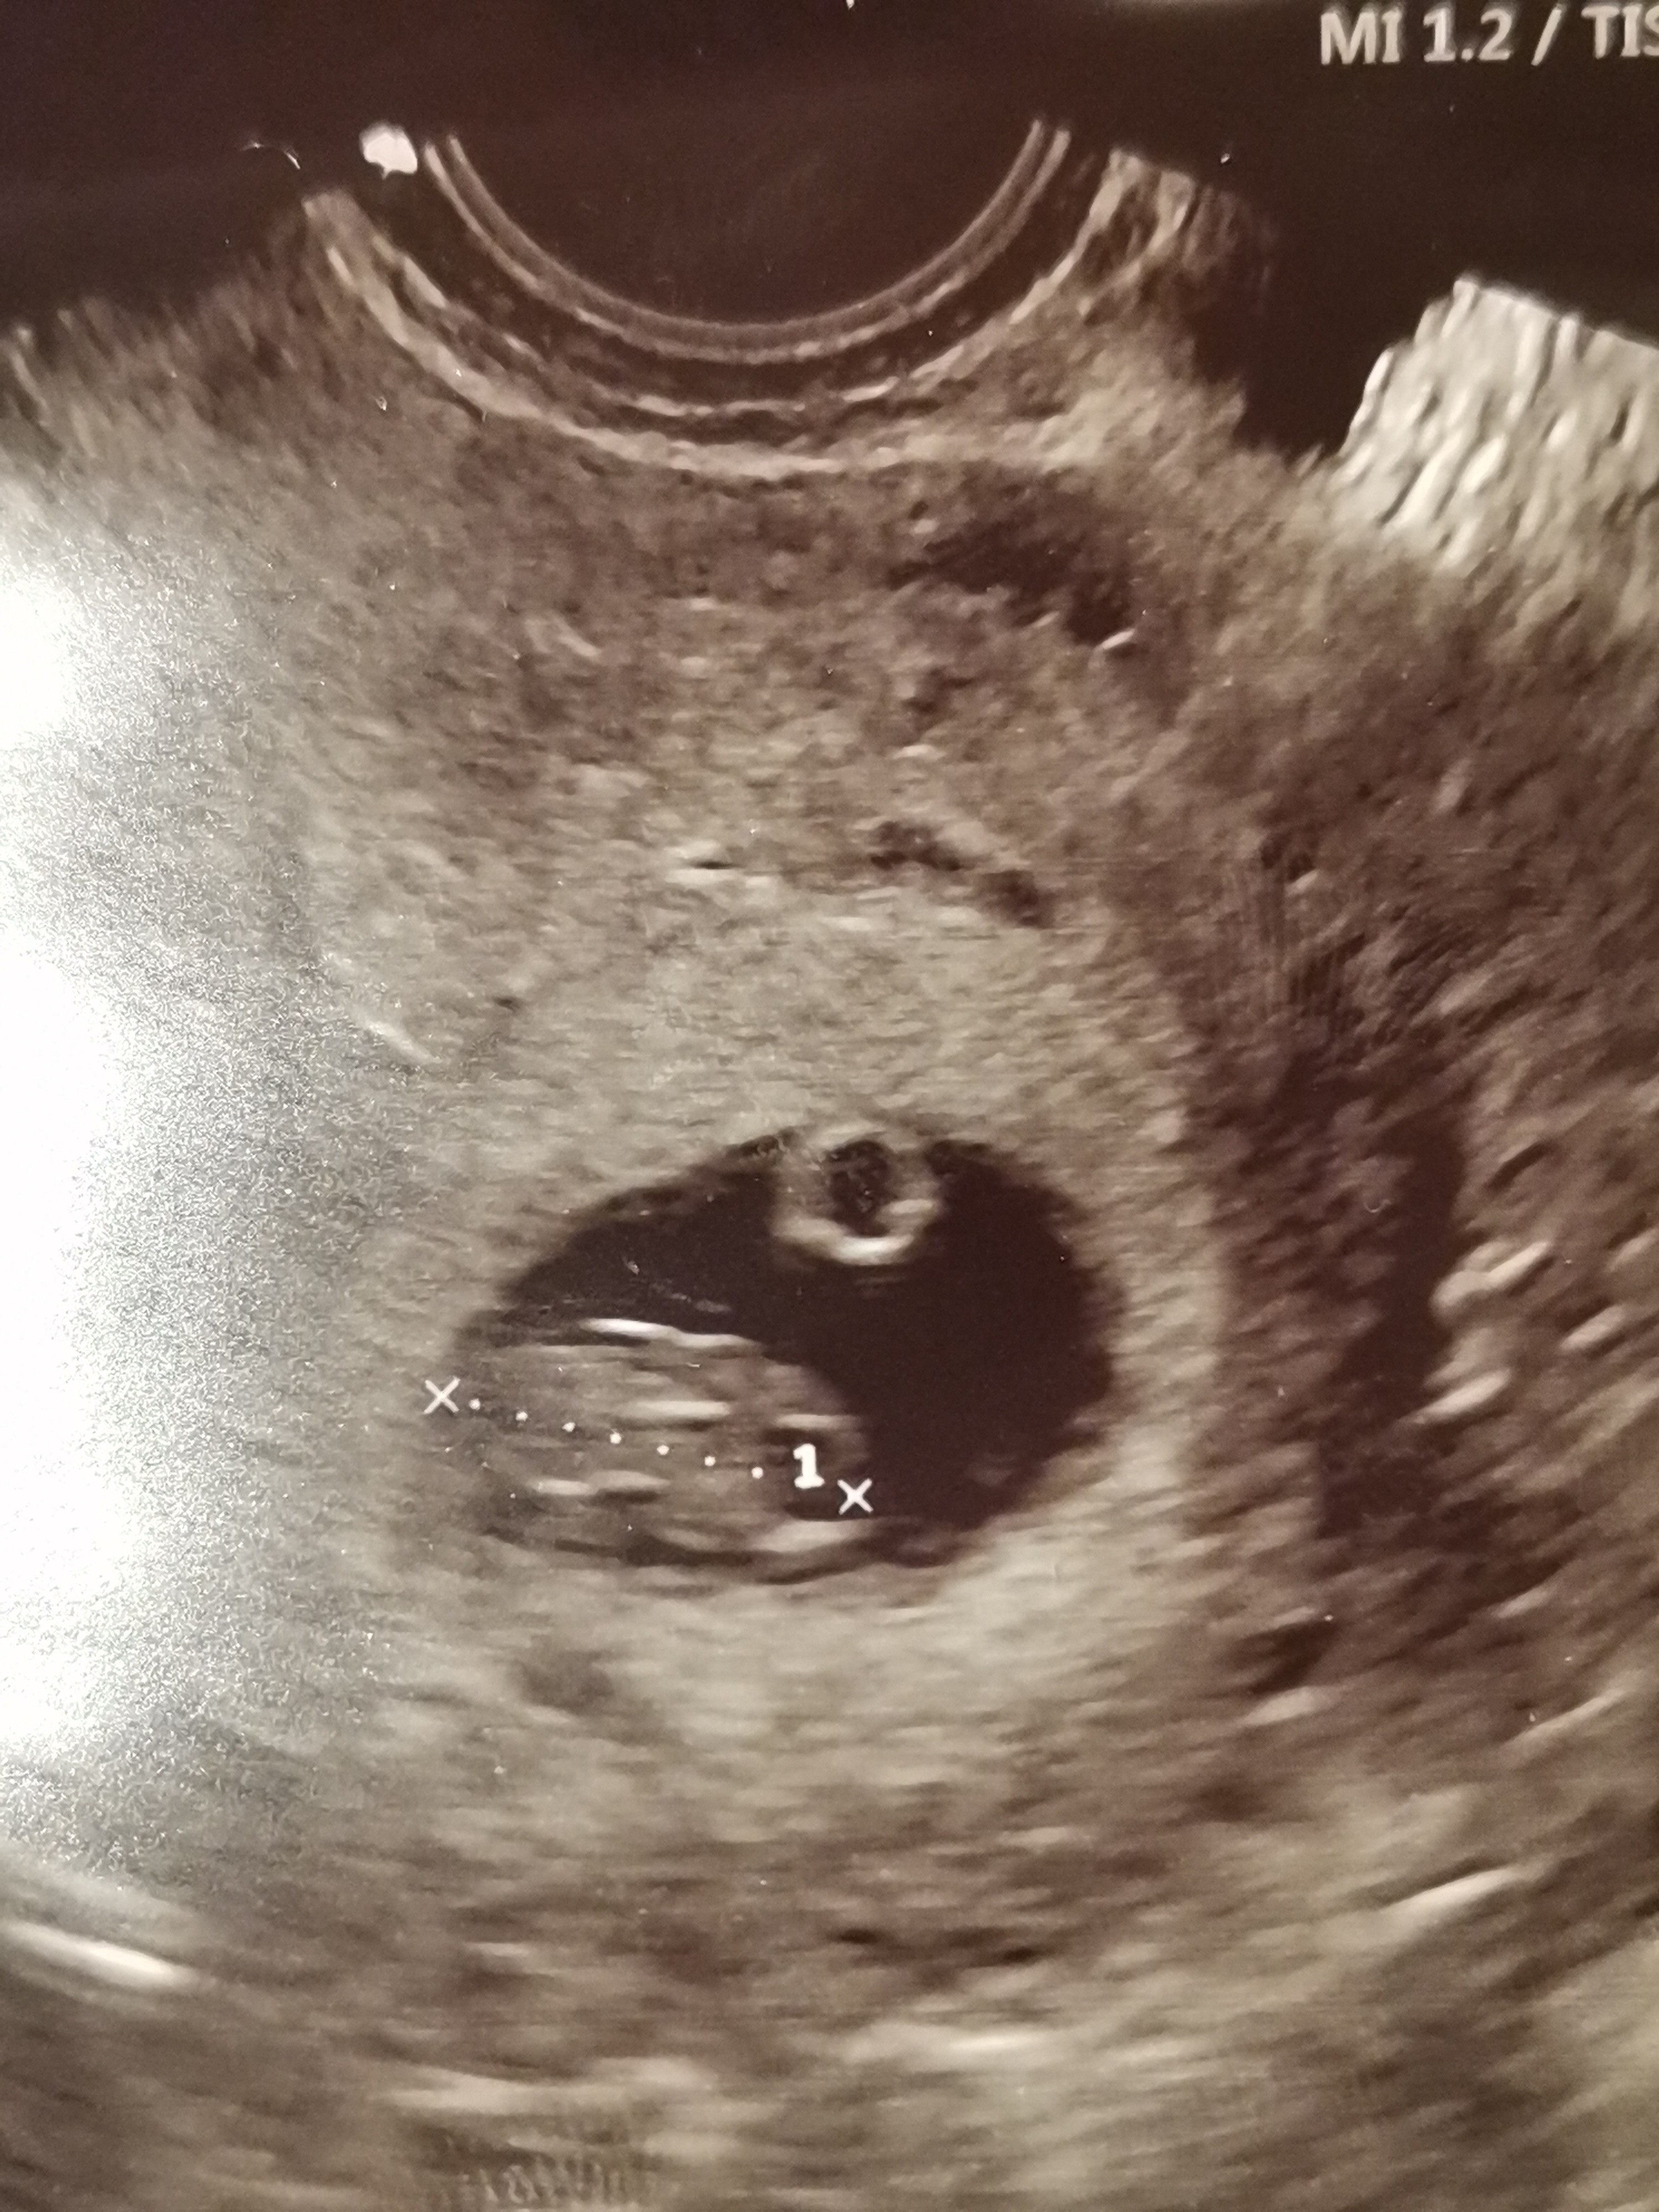

I po wizycie. 7w6d maluszek ma 14,93mm,serduszko bije.

Załączniki

• 1617126779099.jpg

1617126779099.jpg

1,6 MB · Wyświetleń: 121